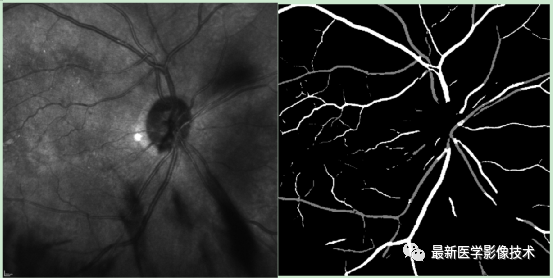

4、验证集分割结果,左图是眼底图像,中间是金标准图像,右图是分割图像

5、测试集部分分割结果